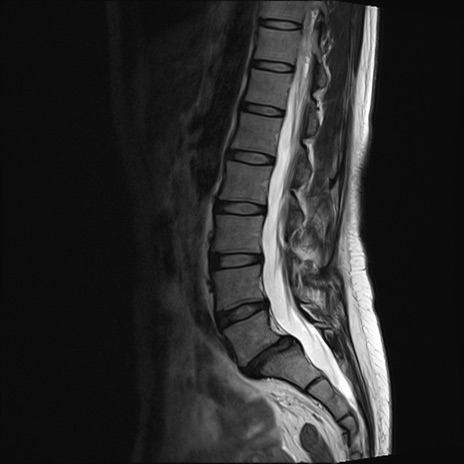

【整形】TIPS症例4 腰椎MRI T2WI(矢状断像)

腰椎MRI

T1WI(矢状断像)